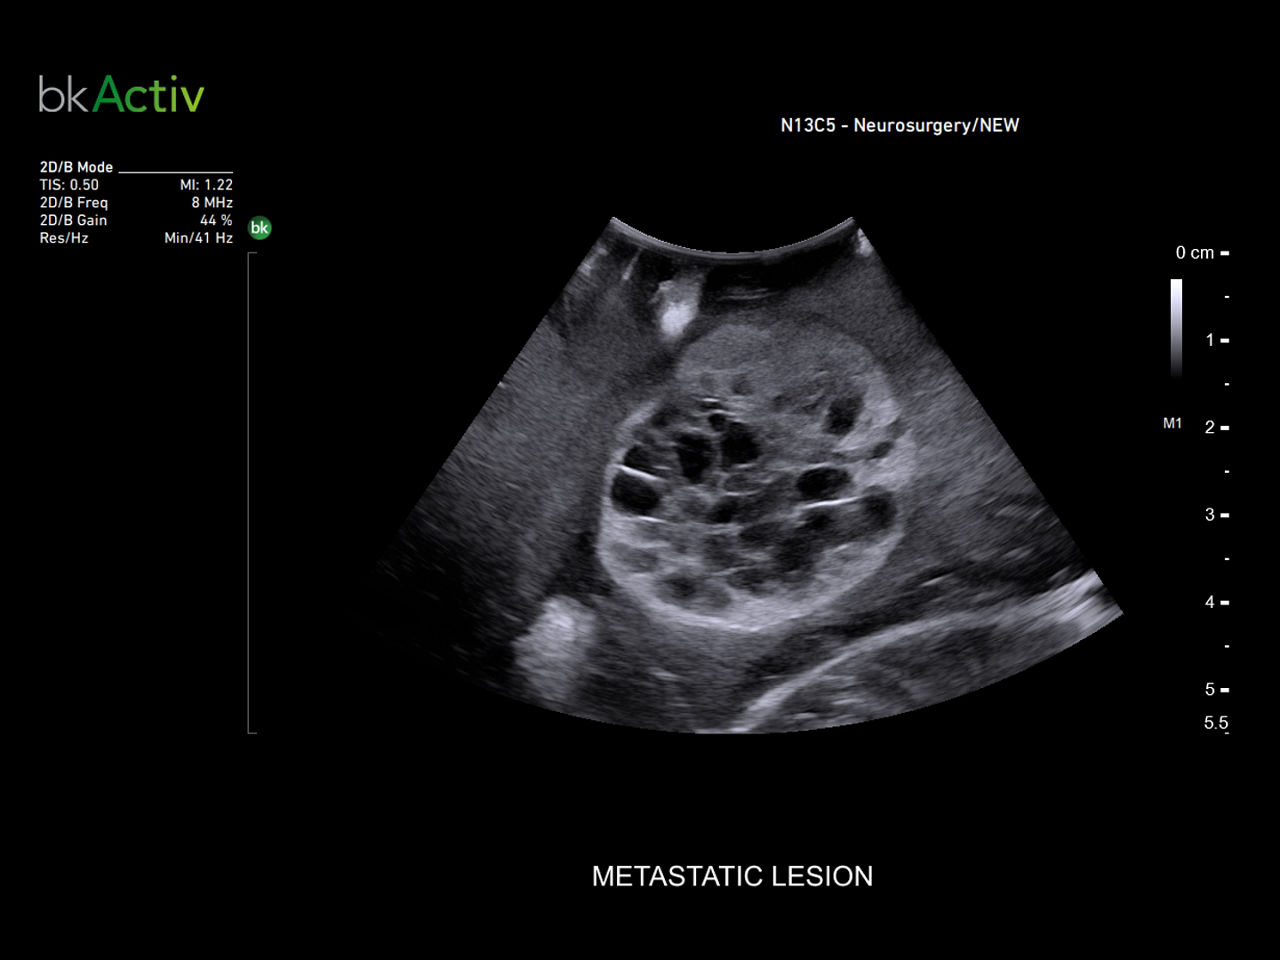

Neuro-oncology

Use intraoperative ultrasound during surgery to assist in the identification of brain shift after pre-operative scans and determine extent of resection and assess for residual tumor.